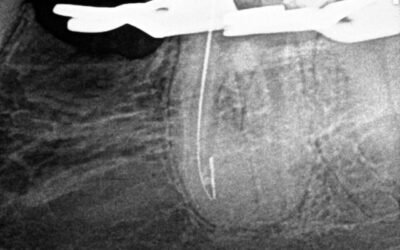

Remoção de broca gates fraturada dentro do canal

De acordo com a imagem abaixo foi feita a remoção de um fragmento fraturado dentro do canal utilizando pontas especificas de ultrassom.